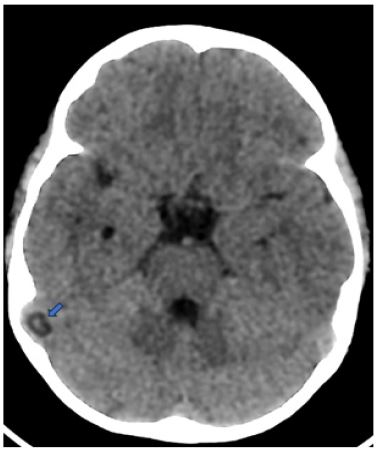

We report the case of a 5-year-old child who presented to the emergency room with febrile behavioral disturbances, including sudden-onset seizures, and visual hallucinations. Brain CT revealed a well-defined, round lesion of cerebrospinal fluid density protruding into the lumen of the right sigmoid sinus, causing a nodular filling defect. Based on its characteristic location and imaging features, the lesion was diagnosed as a giant Pacchionian granulation (Figure 1).

The transverse and superior sagittal sinuses, frequently close to the entrance of a superficial cortical vein, are where GAGs most frequently occur. They show up on CT as well-defined, ovoid or spherical objects of CSF density that protrude into the dural sinus or calvaria and create a focal filling deficit. Their smooth edges, customary location, and absence of edema or parenchymal involvement typically allow distinction, despite the possibility that they resemble dural venous sinus thrombosis.